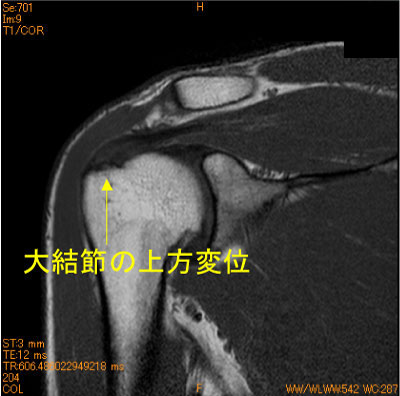

上腕骨大結節不全剥離、棘上筋腱停止部損傷

40代男性。テニスのサーブ時の痛み。水泳歴30年。

棘上筋腱停止部、大結節superior facet部が上方に変位している。